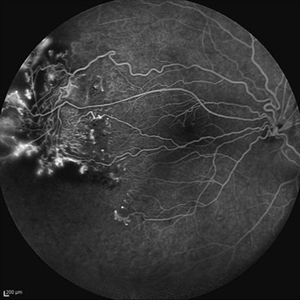

Behcet's Disease Behcet's DiseaseMar 13 2013 by Hamid Ahmadieh, MD Wide field FA of the left eye of a 23-year-old man with retinal vasculitis due to Behcet's disease . Photographer: Solmaz Shahmohammadi , Negah Eye Center, Tehran Imaging device: Heidelberg Spectralis Condition/keywords: retinal vasculitis